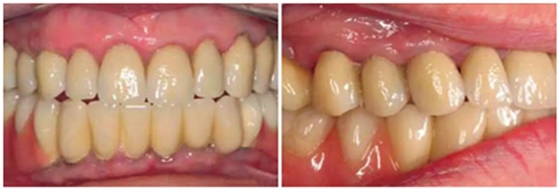

圖17& 18:Katharina Dietz-Epple醫(yī)生(Aalen, Germany)完成的冠修復(fù)(上頜)及可摘局部義齒修復(fù)(下頜)。